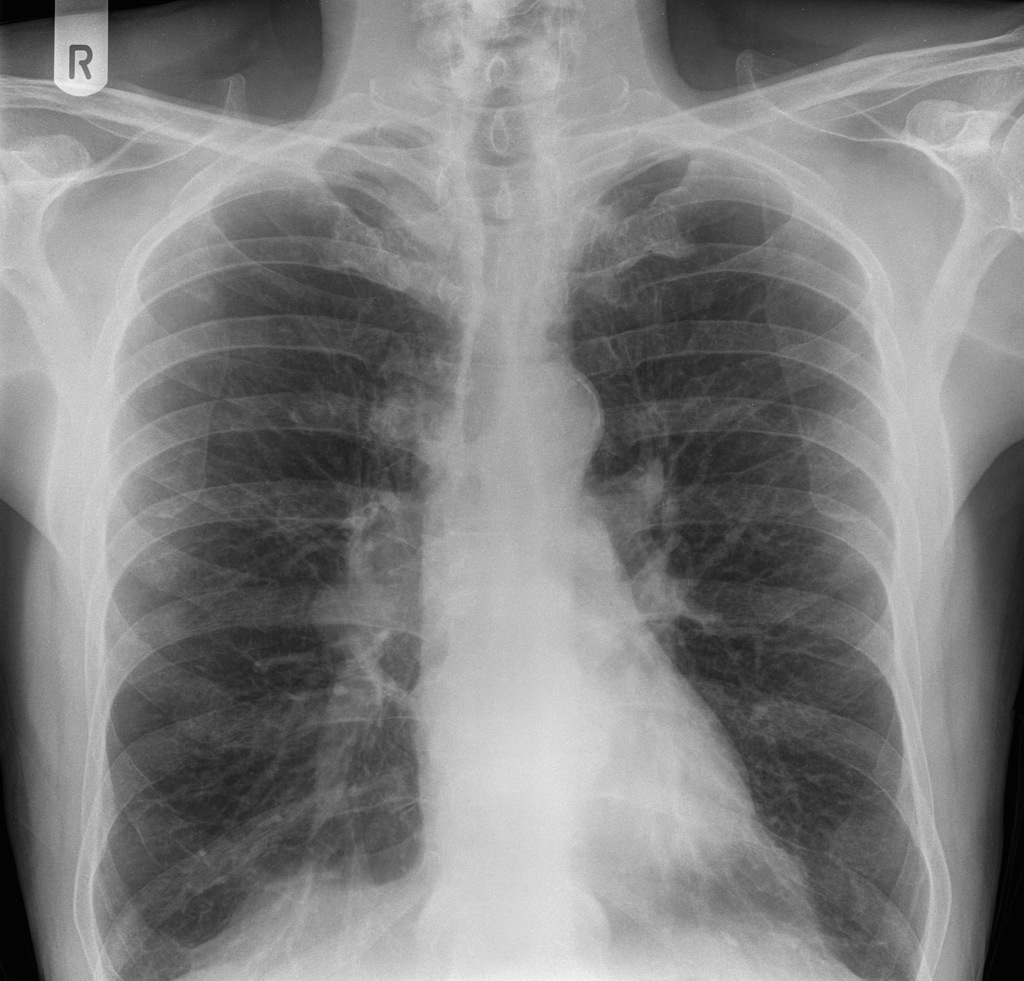

63yo male.

Smoker 45 pkt-years.

CXR: ? hilar mass